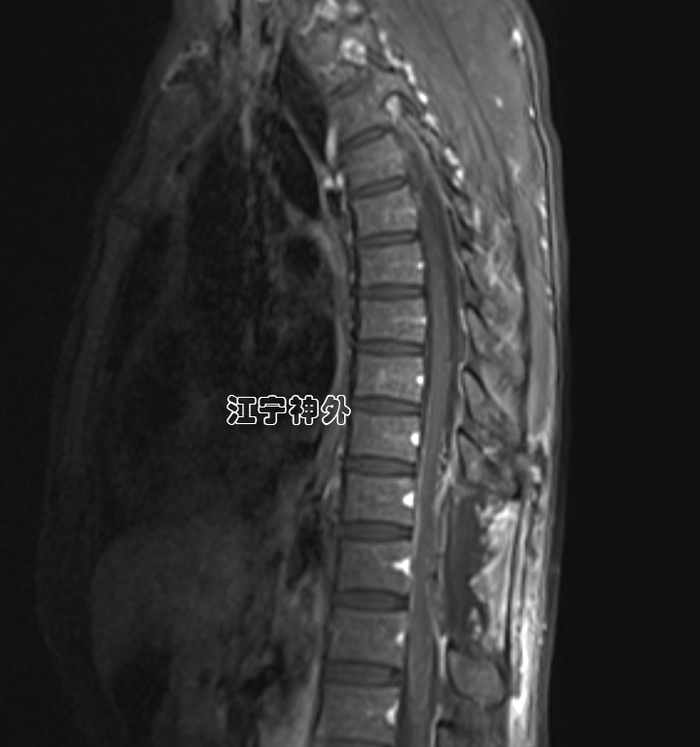

郑主任阅片发现,肿瘤位于胸10水平,属于髓外硬膜下病变,增强不均匀,边界清晰,位于脊髓的左后,脊髓被推向右前方。

经过术前准备,于2月3日在全麻下行肿瘤切除术,手术非常顺利,肿瘤完整全切,根据神经电生理监测,脊髓和神经根保护良好。

术后磁共振显示肿瘤全切,无任何残留;术后两周拆线出院,行走、大小便功能正常,无神经功能缺损。术后病理提示神经鞘瘤。